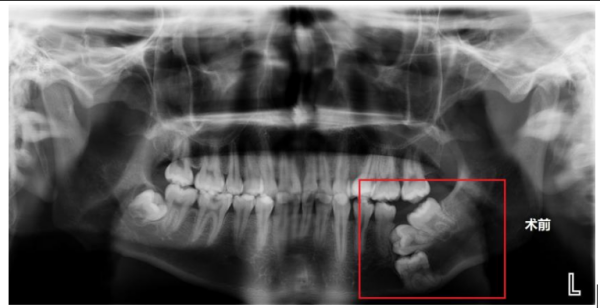

术前X片显示,右下颌骨内没长出来的三颗磨牙呈“叠罗汉”状埋伏

据了解,家住益阳市的王其(化名)自6岁起左下磨牙一直未萌出,家长起初以为仅是发育较晚,未予重视。直至14岁时,王其的磨牙仍未见生长,父母这才带着他去当地立博体育 检查,完善了口腔X片后才发现,王其多年无牙的罪魁祸首竟是其右下颌骨内没长出来的三颗磨牙呈“叠罗汉”状埋伏,由于埋伏牙位置较深,当地立博体育 建议在面部下方皮肤行切口拔除埋伏牙,或者继续观察,等待恒牙自行萌出。因考虑传统手术可能遗留面部瘢痕,王其及家人选择保守观察。